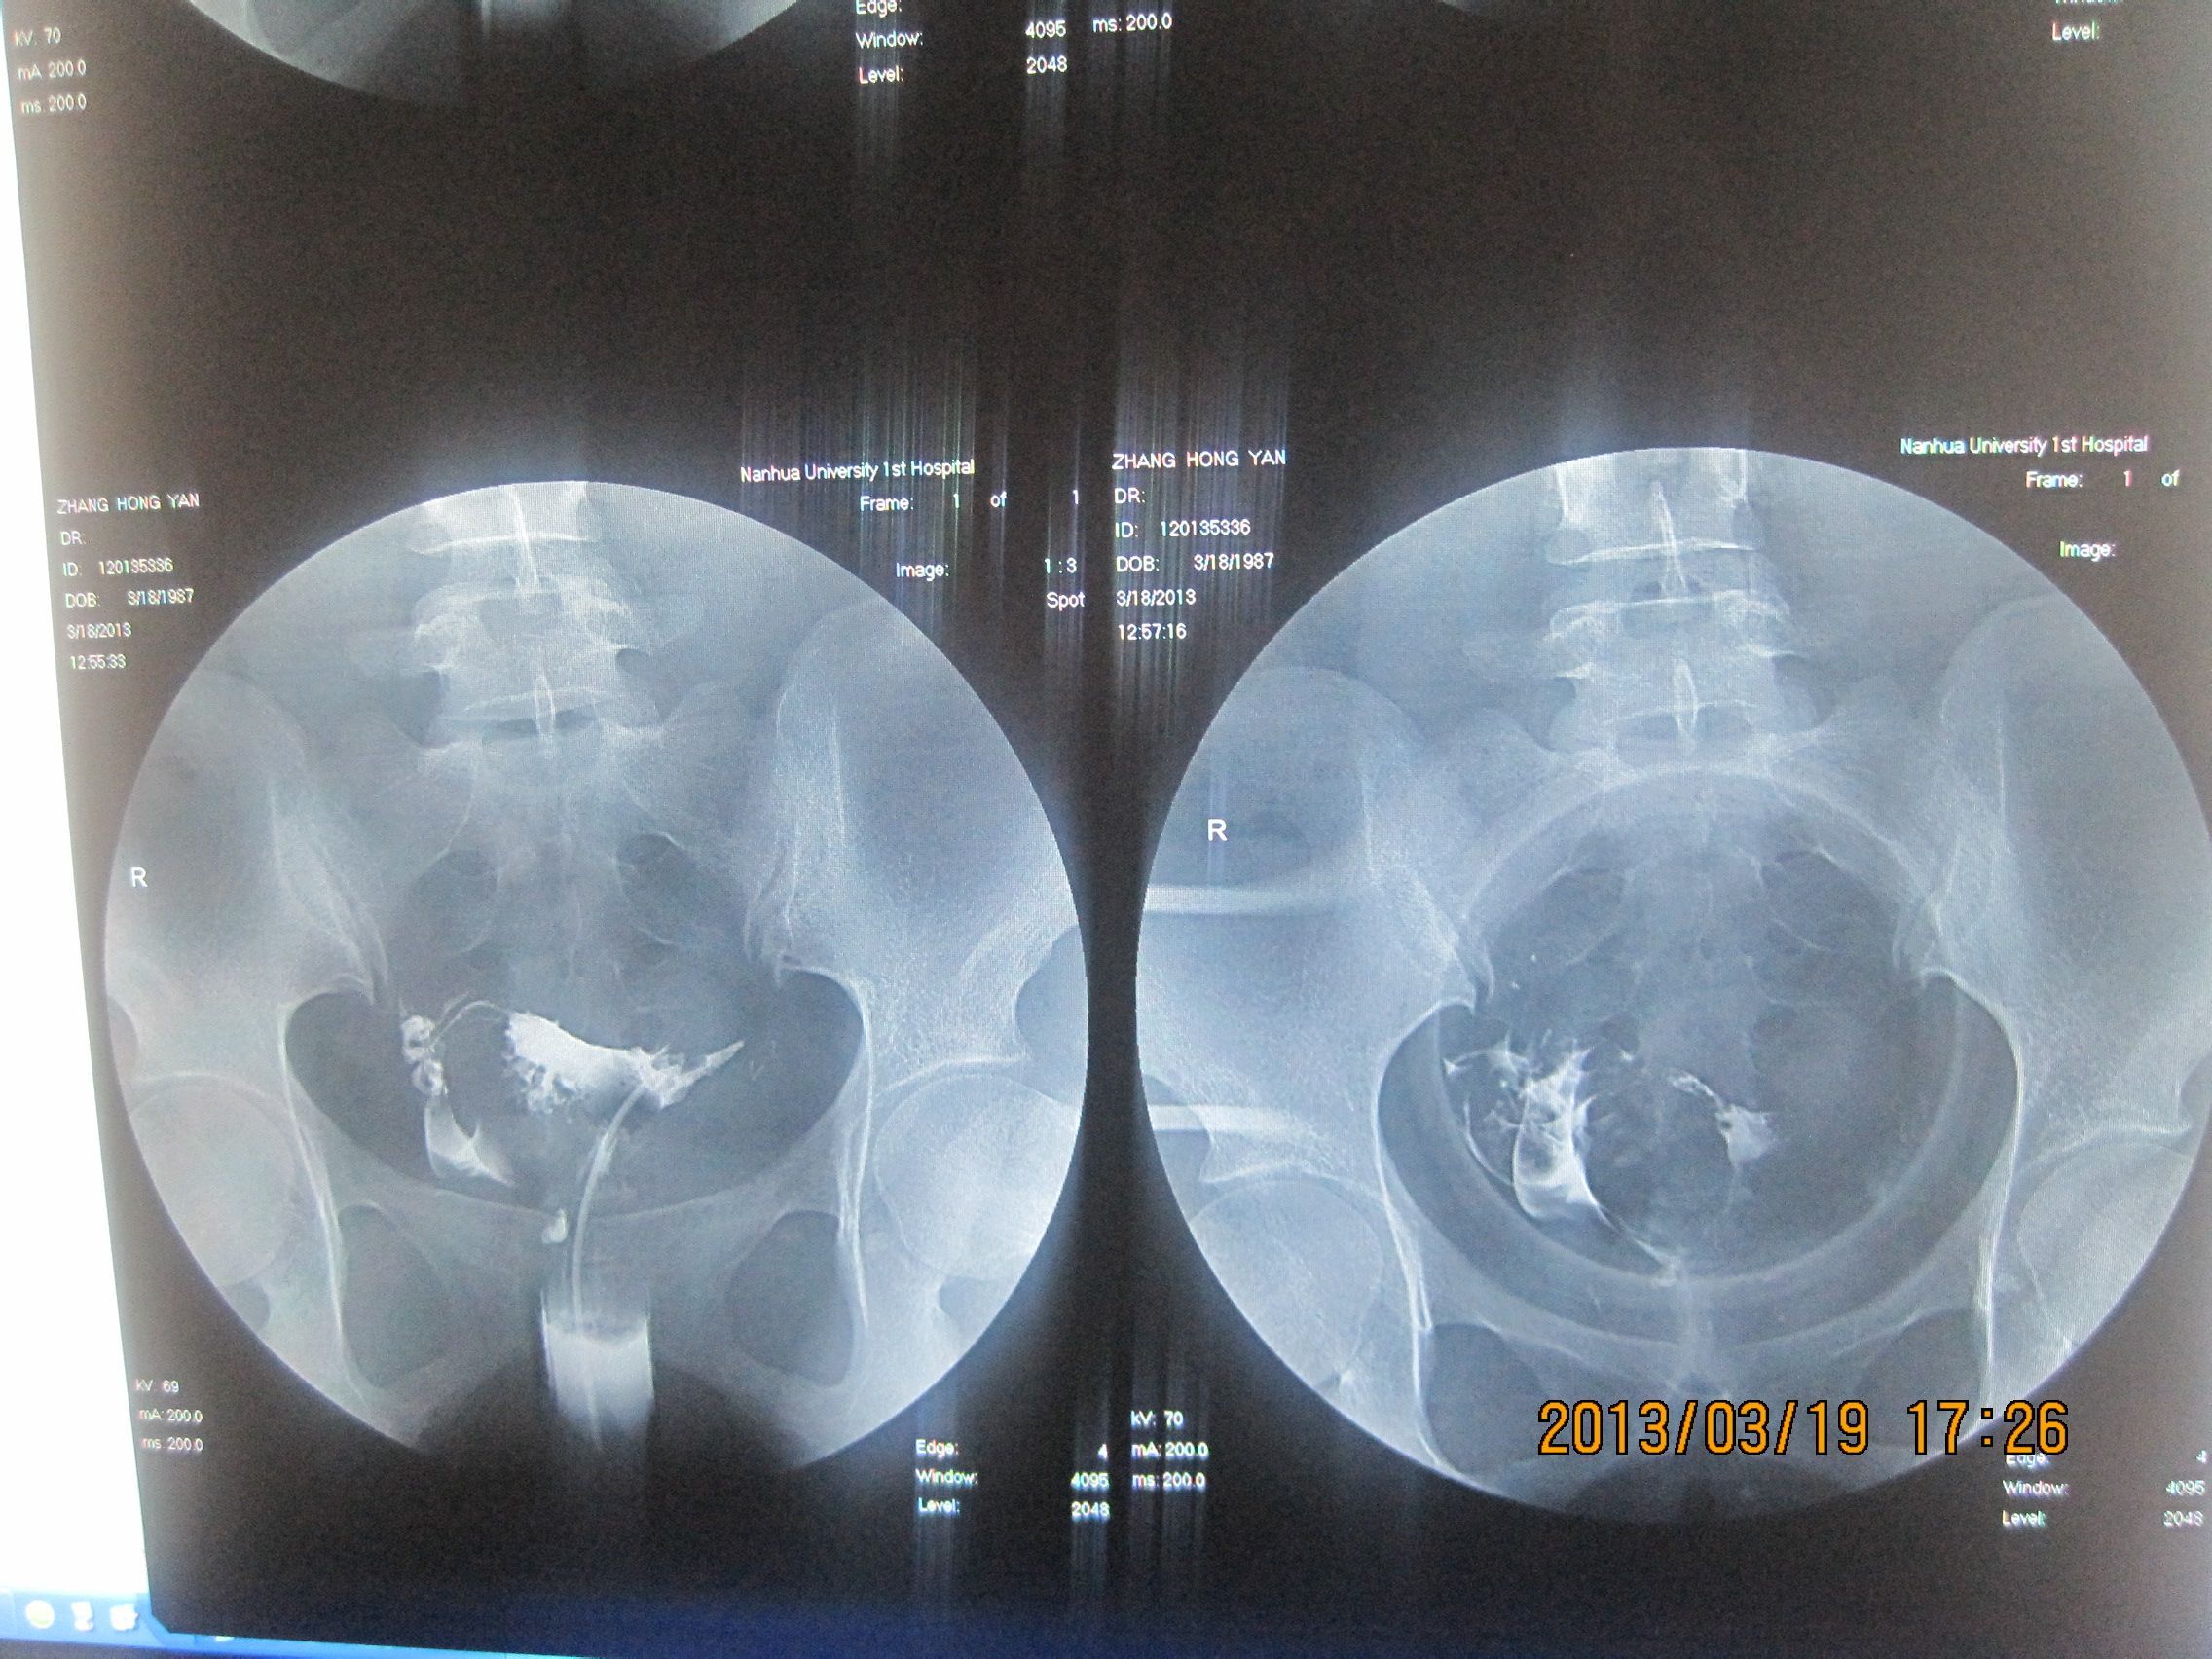

麻烦帮我看下输卵管造影片子 结婚四年一直没有怀孕,各方面的检查也做了不少,都没有什么问题的。刚去做的输卵管造影,请医生帮我看下是否影响怀孕。谢谢 点击展开 匿名用户 2013-03-22 16:27 为您推荐: 其他回答 片子不太清楚,怀疑一侧输卵管堵塞,另一侧输卵管通而不畅。是影响怀孕的。需要治疗。 本雅美_zgqa 2013-03-22 21:17 是输卵管问题,没有怀孕的,输卵管有问题,怀孕了也是有80%的宫外孕的可能的,所以要治疗的, 用逐水舒管汤 匿名用户 2013-03-22 16:49 相关问题 刚拿到输卵管造影的片子 麻烦帮我看下 输卵管造影时医生让我坐起穿裤子过15分钟后再拍最后一张片子,这会影响结果的准确性吗? 输卵管碘油造影片子名字和身份证名字不对证明怎么写